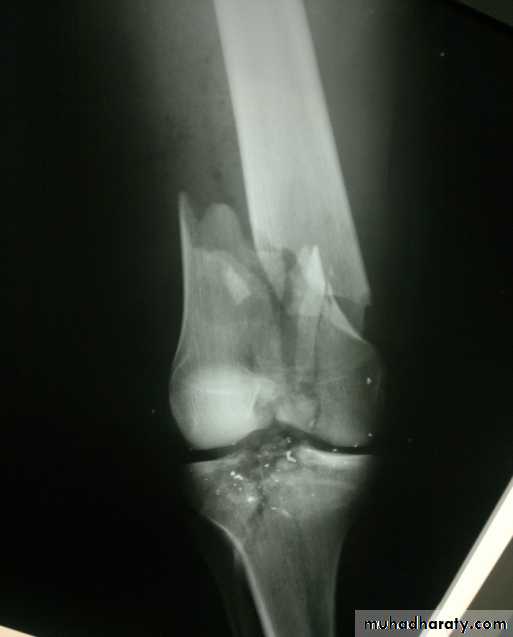

Supracondylar fractures of femur

In young adults after high energy injury.

In elderly osteoporotic after trivial injury.

Intercondylar extension may occur.

Supracondylar fracture with intercondylar extension

In children and adolescents- usually Salter-Harris II injury.Distal fragment tilted backward by gastrocnemius muscle.

Check distal pulses.